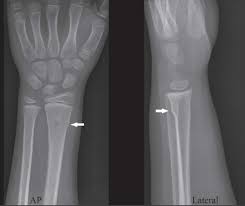

Https Encrypted Tbn0 Gstatic Com Images Q Tbn And9gcs3rkcv6nhn Nzxdau59qvnq7grubo0 Lbikskhfk9l0d9l8eu2 Usqp Cau

Https Encrypted Tbn0 Gstatic Com Images Q Tbn And9gcs3rkcv6nhn Nzxdau59qvnq7grubo0 Lbikskhfk9l0d9l8eu2 Usqp Cau from